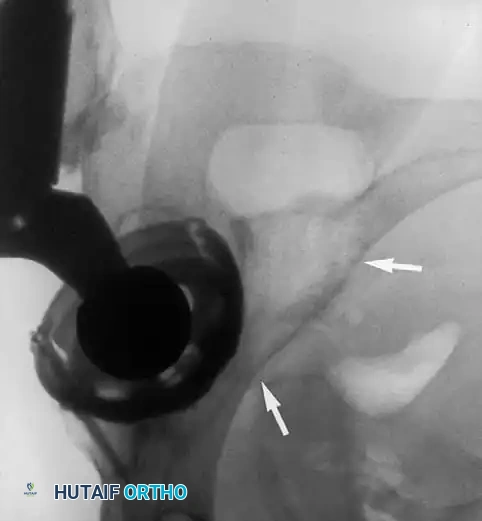

Pitfall: When seating a diaphyseal-engaging stem, prophylactic cerclage cabling of the distal femur is highly recommended to prevent catastrophic intraoperative splitting of the diaphysis during final impaction.

Associated Surgical & Radiographic Imaging